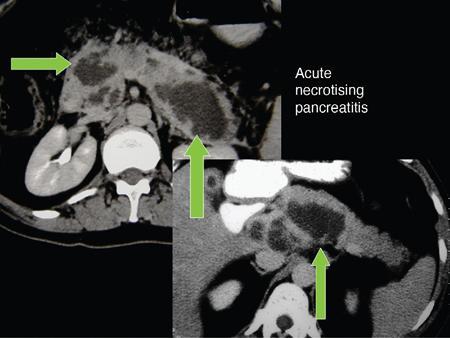

Anirudh Kohli Acute pancreatitis is one of the most dreaded diseases to afflict mankind, in view of its high morbidity and mortality. The single most important factor in reducing the morbidity and mortality of this condition over the last many years has been the role of computed tomography (CT). The incidence of acute pancreatitis is rising especially due to an increasing incidence of gallstones, obesity, as well as an ageing population. Pancreatitis occurs due to a chain of events triggered by a temporary/permanent pancreatic duct obstruction. This leads to activation and release of pancreatic enzymes into pancreatic interstitium and peripancreatic tissues leading to severe auto digestion and necrosis of pancreas and adjacent tissues. Systemically there is release of inflammatory mediators known as cytokines. Tumour necrosis factor is a cytokine which is toxic to acinar cells. These cytokines activate and intensify the inflammatory cascade that may ultimately culminate in multiorgan failure. Clinically severe acute pancreatitis is characterized by two phases, an early phase and a late phase. The early phase is dominated by the systemic effects of release of inflammatory mediators such as cytokines – termed as systemic inflammatory response syndrome (SIRS). Usually there is associated variable multiorgan dysfunction/failure. This phase lasts for a week. When the multiorgan failure lasts 2 days it is termed as mild, multiorgan failure lasting more than 48 hours is considered severe. There is no correlation between the clinical severity of pancreatitis and morphological changes in this early stage. In view of this CT scan is not of much utility during this phase, unless complications are suspected. The later phase is dominated by effects of local complications due to pancreatic/peripancreatic necrosis. Mortality follows this biphasic pattern in early weeks from the systemic effects of multiorgan failure and in later weeks due to local effects, for example infection of necrotic pancreatic/peripancreatic tissues superimposed by organ failure. The Clinical diagnosis of acute pancreatitis requires two of the following three features: If the first two findings are present without any significant SIRS then CT is not required. Acute pancreatitis is a complex disease with a wide variation in the presentation and outcome, ranging from asymptomatic with only biochemical alterations to a fatal outcome. In fact acute pancreatitis is a dynamic disease with continuously evolving appearances on imaging. There are two distinct forms of acute pancreatitis – interstitial oedematous pancreatitis and acute necrotising pancreatitis. Interstitial oedematous pancreatitis is a condition where there is only mild swelling of the pancreas with loss of normal lobulations and a diffuse decrease in attenuation of the pancreas. There may be heterogeneity of the pancreatic parenchyma due to varying degrees of interstitial oedema. This form of pancreatitis runs a mild course and rarely progresses to acute necrotising pancreatitis with its associated complications. In a third of these cases the pancreas may reveal no abnormality on a CT scan. The inflammatory changes may be restricted to the pancreas or extend into the peripancreatic regions. The inflammation in the peripancreatic regions manifests as acute pancreatic effusions. If there is peripancreatic fat necrosis with an oedematous pancreatic gland it is termed as acute necrotising pancreatitis (Figs. 9.17.1–9.17.2). Acute pancreatic fluid collections are enzyme-rich pancreatic juice collections seen in about 40% of patients with acute pancreatitis. The fluid collections occur due to exudation of pancreatic juices into the interstitium of the pancreas and subsequently leakage into the surrounding tissue spaces. These fluid collections are localized only by the anatomic space in which they collect. As the exudative process continues, the parietal peritoneum overlying the pancreas may be disrupted with the inflammatory fluid entering the lesser sac. From the lesser sac the fluid can enter the peritoneal cavity via the foramen of Winslow or by dissecting the peritoneum along the anterior surface of the lesser sac. Posterior extension of the fluid collection in the anterior pararenal space may occur into a potential space between the laminae of the posterior pararenal fascia. Rarely there may be involvement of the perirenal and posterior pararenal spaces. Other pathways of dissection are along the gastrohepatic, gastrosplenic and gastrocolic ligaments. Fluid may dissect along the root of the mesentery into the transverse mesocolon. Collections may extend around the caecum, ascending colon, descending colon and into the lumbar, pelvic and inguinal regions. Large fluid collections may dissect superiorly into the mediastinum or pericardial space. The quantity of fluid in these effusions is variable and can range from a small amount to large quantities (Fig. 9.17.3). Of these collections, 50% resolve spontaneously; the remainder may evolve after 4–6 weeks into pseudocysts. As the collections age, they tend to get localized and walled off, often developing an enhancing wall. A collection should be termed a pseudocyst only when a definite capsule develops and the collection has been static for at least 4–6 weeks. The risk of complications such as rupture, infection and haemorrhage increases with the age of the collection. Large collections of fluid are usually associated with a lesser degree of pancreatic necrosis as compared to extensive pancreatic necrosis associated with a lesser amount of fluid collection. Acute necrotising pancreatitis is a fulminant form of pancreatitis in which there is necrosis of the pancreas, that is nonviable pancreatic tissue. A contrast-enhanced CT is essential as it is the ideal means to demonstrate necrosis as well as to determine the extent of necrosis. These areas of nonviable pancreatic tissue do not enhance as compared to viable pancreatic tissue, which demonstrate significant enhancement. The extent of pancreatic necrosis has been found to correlate extremely well with the extent of necrosis found at surgery. The size, location and extent of pancreatic necrosis are very variable. These areas may be diffuse or focal, small in size to complete glandular involvement. These necrotic areas have a very important bearing on the course of pancreatitis, as they are liable to undergo secondary infection and form pancreatic sepsis. In addition, the more extensive the pancreatic necrosis the greater is the morbidity and mortality. Patients with no pancreatic necrosis have been found to have a 0% mortality and a 6% complication rate, whereas patients with pancreatic necrosis have a 23% mortality rate and an 82% complication rate. A variety of laboratory tests are available to detect pancreatic necrosis, such as a rise in the serum methemalbumin, quantitative estimation of C-reactive protein and urinary trypsinogen-activated peptide. CECT is still the most accurate modality to detect pancreatic necrosis. Pancreatic necrosis may be seen in the pancreas only, peripancreatic tissues also or only in the peripancreatic region. Isolated peripancreatic necrosis occurs due to disruption of the peripheral ductules with extravasation of activated pancreatic enzymes, may be seen in up to 20% of patients who require operative/interventional management of their necrotising pancreatitis. These patients with only peripancreatic necrosis have a better prognosis. This essentially represents retroperitoneal fatty tissue necrosis appearing as heterogeneous areas of liquid and nonliquid components. Over time necrosis evolves and liquefies as well as the liquid component resorbs. Generally if the liquid component is 2 cm or less it will resorb, while fluid collections 5 cm or more rarely resorb. If pancreatic necrosis is not resorbed it may get walled off or with time or may become infected. Encapsulation occurs between the third and fourth weeks. It is important to differentiate sterile from infected necrosis as sterile necrosis rarely needs surgery, whereas infected necrosis requires long-term antibiotic therapy and/or some kind of imaging/surgical intervention. According to the Atlanta 2012 classification, all areas of pancreatic necrosis are termed as acute necrotic collections. This represents a combination of pancreatic/peripancreatic fat necrosis with peripancreatic effusions. On CT, there is a spectrum of findings – solid, liquid containing debris (these may be nonwalled off/partially walled off). Sonography and MRI have advantages over CT scan in demonstration if the contents are pure liquid such as acute pancreatic effusions or have some nonliquefied components such as acute necrotic collections. Pseudocysts are round or oval encapsulated fluid collections containing only liquefied components. It takes 4 weeks for the granulation tissue to develop. On CT, a pseudocyst appears as a well-defined fluid collection with a thin capsule. The most common location for pseudocysts is the lesser sac, though they may be found anywhere in the mediastinum, abdomen or pelvis as they may dissect along fascial planes, along vessels and through capsules of solid organs. Pseudocysts in the bowel, though reported, are relatively rare, as the bowel wall is a strong barrier to the effect of proteolytic pancreatic enzymes. When the contents of the pseudocyst are heterogeneous or uniformly increased in attenuation, the possibilities of infection or haemorrhage should be considered. Focal areas of increased density within the fluid collection usually indicate haemorrhage. Complicated, enlarging or symptomatic pseudocysts require percutaneous catheter or surgical drainage. Infected pseudocysts are treated by percutaneous drainage. The management of a noninfected pseudocyst is controversial. Surgical treatment is only undertaken when the wall is mature after several weeks. Large pseudocysts greater than 5 cm in size can easily be drained percutaneously using intercostal drainage tube or pigtail catheter or endoscopically via the stomach. The cure rates are reported to be 85% with percutaneous drainage, the drainage period averaging about 20 days (Figs. 9.17.4–9.17.5). Walled off necrosis – as pancreatic/peripancreatic necrosis matures and evolves, an interface develops between necrosis and adjacent fatty tissue and an enhancing thickened wall is seen, resulting in a well-defined fluid collection with necrotic debris and fat necrosis. This is the end stage in the evolution of an acute necrotic collection. It is important to differentiate a pseudocyst from walled off necrosis, as a pseudocyst requires drainage and walled off necrosis requires surgical removal (Figs. 9.17.6–9.17.9). Sepsis is a major complication of pancreatitis and is accompanied by a high incidence of mortality and a prolonged hospital stay. Pancreatic sepsis may occur following secondary infection of pancreatic and/or peripancreatic necrosis, acute pancreatic fluid collections and pseudocysts. The only specific sign to demonstrate sepsis is the presence of gas in a collection. This occurs due to secondary infection by coliform/anaerobic organisms. This sign is unfortunately not common and seen in only one-third of cases. Gas is seen in the fluid collection as very dark well-defined air attenuation bubbles. Occasionally gas may be present due to a gastrointestinal fistula or previous surgery. Fat necrosis is seen in peripancreatic collections. This should not be confused with air bubbles, which are indicative of sepsis. The differentiation is easy to understand by CT, the values of fat ranging between – 20 HU and – 80 HU, and of air being >–300 HU. Also air bubbles have well-defined margins and are homogeneously jet black, whereas fat is nonhomogeneously grey with ill-defined margins. Since the presence of air is seen only in a small percentage of patients with pancreatic sepsis, the only other means to diagnose pancreatic sepsis is by CT-guided aspiration. All sites of fluid collection, parenchymal necrosis and peripancreatic necrosis are subjected to CT-guided aspiration. This is a tedious process and requires a dedicated interventional radiologist as there are often more than 5–6 sites from which it may be necessary to obtain samples. A fresh needle and syringe are used for each site, as it is important to know which site has sepsis and which is sterile. Care is taken not to transgress the large bowel as the colon has a large number of bacteria, and transgressing it could result in colonic bacteria contaminating the CT-guided aspiration sample, with falsepositive results. Further, colonic bacteria may be inoculated into a sterile acute pancreatic fluid collection or necrosis thereby converting a sterile collection into an infected one (Fig. 9.17.10). Complications of the procedure can be pneumothorax if the pleura is transgressed, haemorrhage due to trauma to a vessel, and secondary infection. Pancreatic sepsis is treated by surgical debridement, necrosectomy and drainage through thick tubes. It is crucial from the management point of view to differentiate an abscess from infected necrosis. An abscess may be treated by percutaneous drainage, whereas infected necrosis developing in relatively solid tissue can be treated by surgical debridement alone. Imaging-guided percutaneous drainage is the first step in treating pancreatic sepsis especially patients who are very ill and cannot undergo surgery. Initially pig tail catheters were used but these are notorious to get blocked as the largest bore of a pigtail catheter is 12 F. Pancreatic sepsis contains a large amount of necrotic debris, this blocks the catheters can be cleared by flushing the catheter, but this always raises the possibility of introducing secondary infection. To circumvent this issue large-bore ICD catheters have been introduced. These range from 16 F to 30 F. A safe window is necessary, not transgressing bowel or vasculature. It is quite easy to insert these tubes percutaneously under CT. A bit of initial manipulation and force is required to pierce the abdominal musculature. These large-bore drainage tubes have been very effective unless the infected necrosis is solid with minimal liquefied contents or a safe window for placing an ICD catheter is not available. CT is also invaluable in surgical planning and in the follow-up of postoperative patients to evaluate any fresh collection and also to determine whether the drains are well sited or not (Fig. 9.17.11).